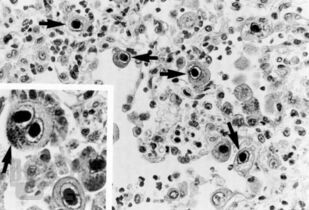

В учебно-методическом пособии представлены современные данные об этиологии, эпидемиологии и патогенезе цитомегаловирусной инфекции у детей. Рассмотрены особенности клинической картины в зависимости от путей инфицирования детей, приведены алгоритмы диагностики, дифференциальной диагностики, лечения и профилактики данной инфекции. В приложении приведены тестовые задания и типовые клинические ситуационные задачи с эталонами ответов для самостоятельного контроля, а также список литературы.